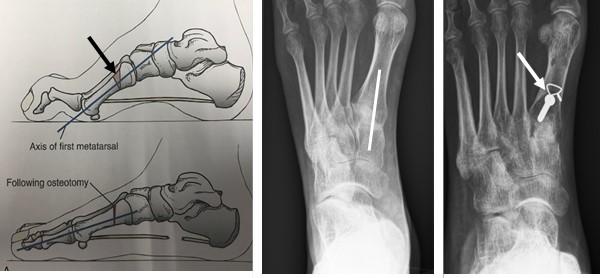

Extenderende Osteotomie 1e straal

Hierbij wordt de grote teen omhoog geplaatst door een botwigje uit te zagen aan de basis van de grote teen. Door dit wigje te verwijderen kan de grote teen omhoog komen waardoor de holling in de voet minder wordt. De voet wordt dus platter en beter belastbaar. Op de plaats waar we het botwigje hebben verwijderd plaatsen we een RVS schroefje en ijzerdraadje om het middenvoetsbeentje van de grote teen op de juiste positie te houden. Zodra het bot genezen is, is de schroef niet meer nodig en kan bij klachten evt worden verwijderd.

Figuur 4: Het bovenste linker plaatje is een schematische weergave van de “osteotomie”. Het driehoekje bij de pijl wijst naar de wig die uitgezaagd wordt. Het plaatje eronder laat de situatie zien na verwijderen van het wigje. Het middelste plaatje laat een voetfoto van een patiënt zien voor de operatie, de witte streep is de plaats van het litteken. het meest rechtse plaatje is na de operatie. Bij de pijl zie je de schroef en het ijzerdraadje om de botdelen op de juiste positie te houden.